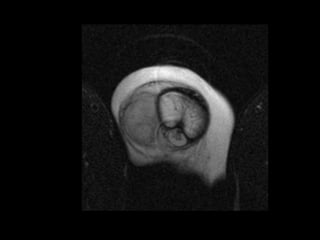

Diagnostico

•    Palpacion de hematoma

•    Incurvarcion

•    Uretrografia retrograda

•    Cavernosografia

•    USG Doppler

•    RMN

Clinica

•    Dolor 20%

•    Chasquido 15%

•    Edema 30%

•    Hematoma 40%

•    Uretrorrgia16%

•    Reteción urinaria 5%